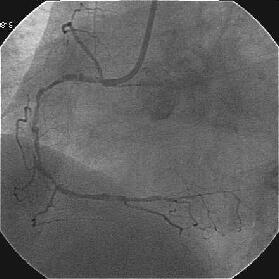

�܂�pre CAG.

|

|

|